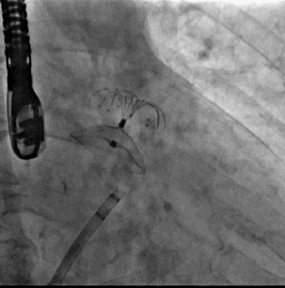

2. 经右桡动脉置入Sentinel CPS系统,释放于头臂干、左颈总动脉位

6. Sentinel CPS系统

Sentinel CPS系统在另一患者中應用捕抓到的左心耳血栓